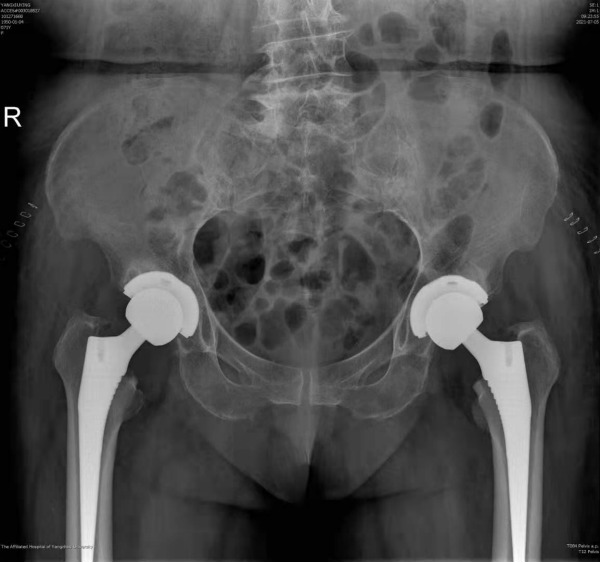

72日,我院骨科关节重建组徐松诊疗团队顺利为一名双侧髋关节骨性关节炎患者实施了双侧人工全髋关节置换手术。该手术为我院首次同期为双侧股骨头坏死患者进行人工全髋关节置换手术,突破了需要分两次进行全髋关节置换的治疗传统,缩短该类疾病的治疗周期,减轻了该类患者的经济负担,标志着我院骨科关节重建技术水平迈上新的台阶。

杨女士今年71岁,长年遭受双侧髋部疼痛的困扰,基本丧失行走能力和劳动能力生活质量受到严重影响。近日,她慕名来到我院骨科就诊,骨科副主任医师徐饶仔细读片后判断杨女士双侧髋关节疼痛的主要原因是双侧髋臼发育不良继发双侧股骨头坏死所致。目前杨女士的双侧股骨头已经磨损变形,关节间隙消失且疼痛明显,已经具备了进行双侧全髋关节置换的指征。

考虑到手术风险的增大,术前麻醉科副主任张建友、副主任医师姚宏苏对患者进行了详细的风险评估,并制定了相应的风险预案,最终手术进展顺利按照快速康复计划,该患者在术后第3天即已扶助行器下床进行功能锻炼,术前双侧髋关节疼痛及下肢不等长症状已完全消失